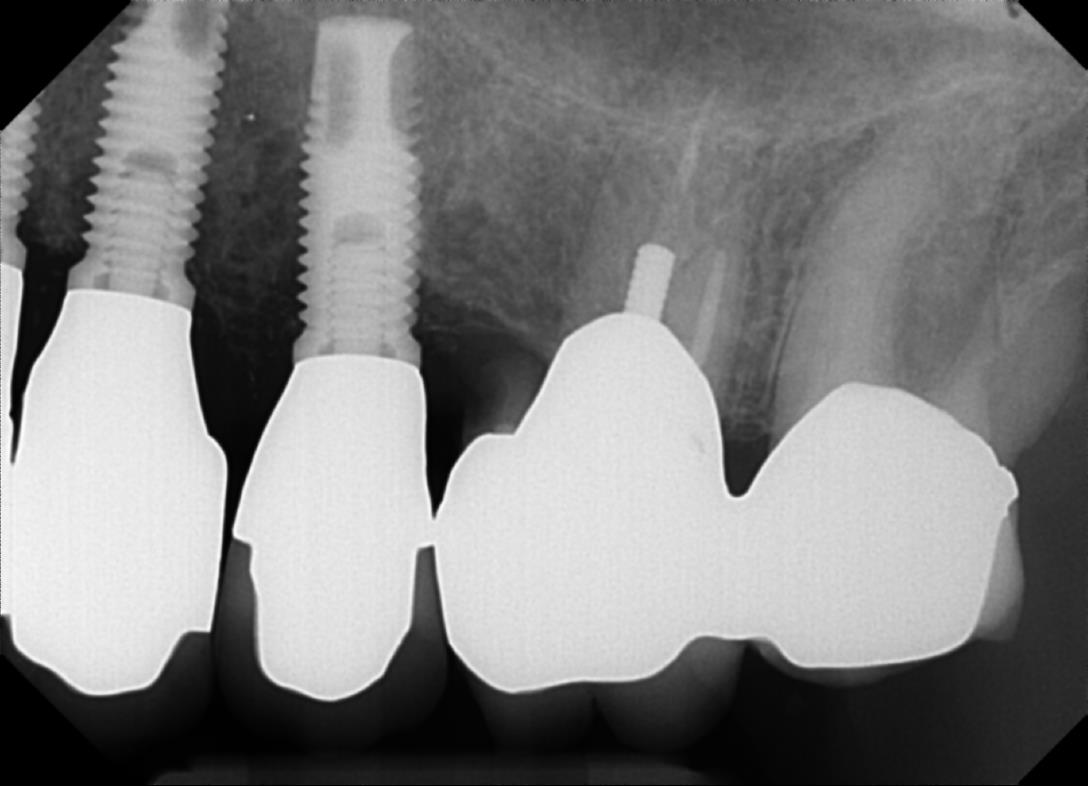

Brånemark dental implants on the left of the imageRemember that patient who got the first Brånemark implant in 1965? She died a while ago from old age, but her dental implants were still perfect right up to the end. That's over 40 years!